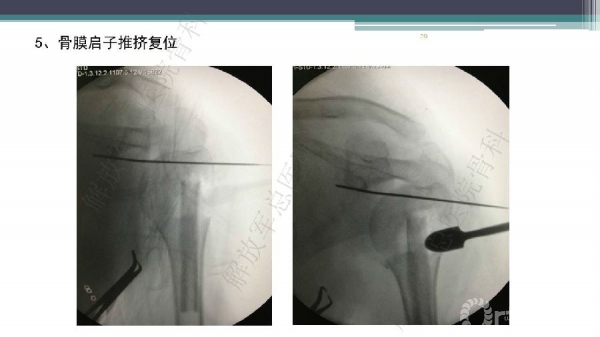

导 语:肱骨近端骨折仍是最常见的骨科损伤之一,尤其好发于老年人群。移位型肱骨近端骨折通常需要手术治疗,但是由于骨折粉碎、骨质较差,手术治疗往往会比较困难。随着锁定钢板的发明,使得并发症显著降低。但仍存在一些问题,对于内侧皮质不连续缺乏内侧可靠支撑,合并老年骨质疏松的病人,锁定钢板吊臂样结构就无法满足力学要求,随着康复锻炼可能出现断板、断钉、螺钉切出肱骨头等并发症。本期解放军总医院骨科专家们对老年肱骨近端骨折的问题与创新手术技术进行了详细讲解。